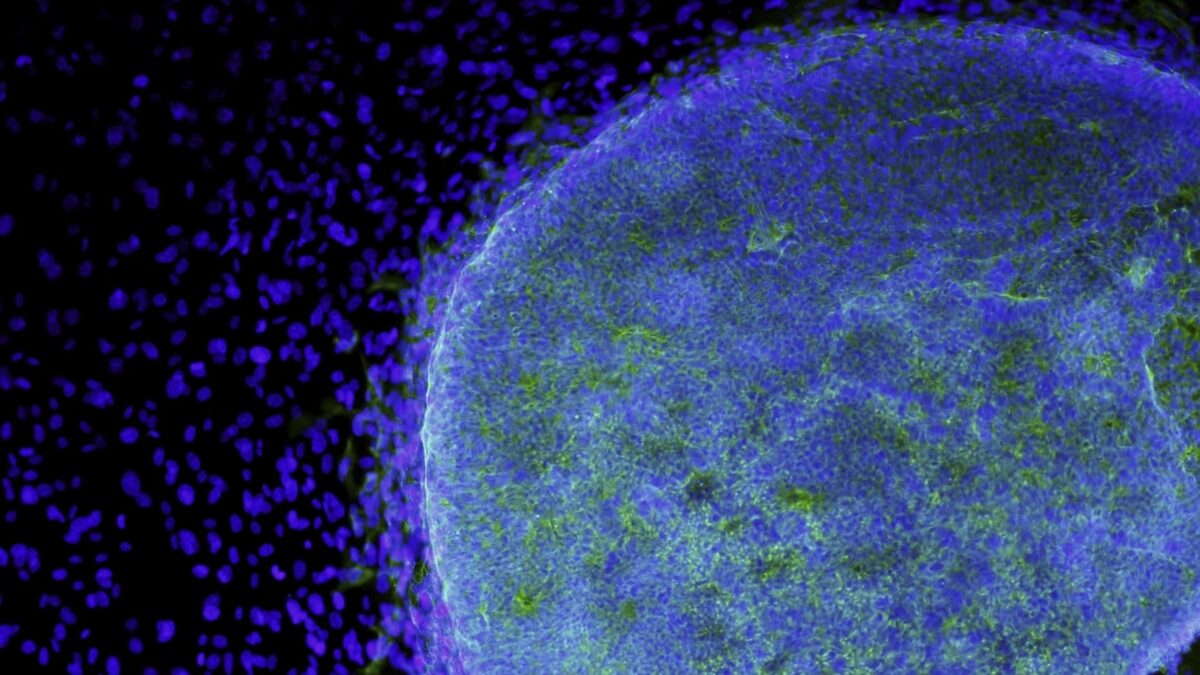

Το έγγραφο περιγράφει λεπτομερώς το πώς οι επιστήμονες πήραν ανθρώπινα εμβρυϊκά κύτταρα και τα επαναπρογραμμάτισαν, ώστε να γίνουν βλαστοκύτταρα. Αυτά εισήχθησαν στη συνέχεια σε 132 έμβρυα μακάκων με μακριά ουρά, έξι ημέρες μετά τη γονιμοποίηση.

Τα έμβρυα αναπτύχθηκαν για 19 ημέρες, πριν τερματιστούν από τους ερευνητές. Οι ερευνητές κατασκεύασαν τα ανθρώπινα βλαστοκύτταρα για να παράγουν μια φθορίζουσα πρωτεΐνη, προκειμένου να υποδείξουν ότι τα έμβρυα περιείχαν ανθρώπινα κύτταρα.

Αν και και τα 132 έμβρυα περιείχαν ανθρώπινα κύτταρα επτά ημέρες μετά τη γονιμοποίηση, η μελέτη δείχνει ότι το ποσοστό των ανθρώπινων κυττάρων μειώθηκε, όσο περνούσαν οι μέρες.